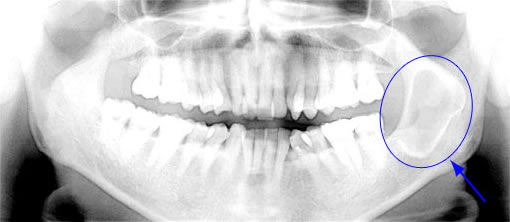

• 普通に生えている親知らず

• 真横にしかも骨に埋まっている親知らず

確かに上のレントゲン写真の様に顎に埋まっている親知らずを抜歯する場合は、抜歯後、多少腫れたり痛みもでるでしょう。しかし、普通に生えている場合は、痛みも腫れもほとんどありません。

症例1:親知らずの抜歯

埋まっている親知らずを抜歯すると、半年程度できちんと骨が出来上がってきます。

• 初診時

右下の親知らずと手前の歯が下あごに埋まっています。

• 抜歯2週間後の状態

抜歯した部分は、徐々に骨が出来上がってきます。

抜歯後、半年程で骨は出来上がります。

健康保険適用のため治療費は約4,000円(3割負担)。

治療期間は、抜歯後1週間ほどで抜糸を行い問題なければ終了。

治療のリスクは、術後の疼痛(ドライソケット)・術後の感染・下歯槽神経麻痺・上顎洞との交通などがあります。

症例5:下顎の骨の中に出来た嚢胞または腫瘍

写真の右側(矢印の部分)にX線透過像(影)が認められます。

下顎の骨の中に見られる嚢胞(膿の袋)です。(腫瘍の場合もあり)

症状は無く、この様なレントゲンを撮影したときにたまたま見つかるケースがほとんどです。

処置は摘出する必要がありますが、病巣が大きいので入院が必要です。

速やかに大学病院もしくは総合病院の口腔外科にご紹介いたします。